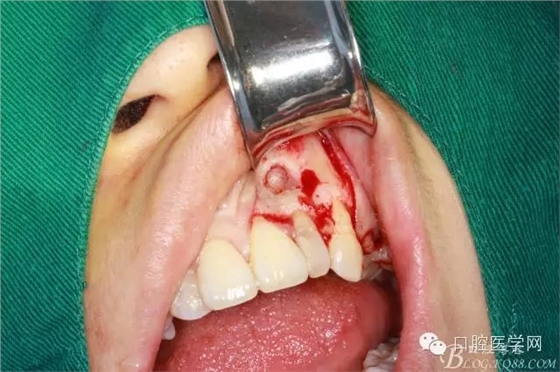

翻全厚瓣后暴露骨面

確定根長(根管充填時已確定)

去 骨

可見囊腫